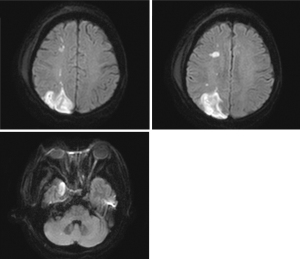

After admission, laboratory tests indicated random blood glucose (GLU) level of 12.74 mmol/L (normal value ≤11.1 mmol/L), base excess (BE) level of −3.4 mmol/L (normal range, −3 to +3 mmol/L), β-hydroxybutyric acid (β-Hb) level of 3.61 mmol/L (normal range, 0.02–0.27 mmol/L), white blood cell count (WBC) level of 17.44×109/L (normal range, 3.69–9.16/L), procalcitonin (PCT) level of 0.46 ng/mL (normal range, 0.00–0.05 ng/mL) and interleukin-6 (IL-6) level of 317 pg/mL (normal range, 0.00–7.00 ng/mL). Considering the presence of infection and diabetic ketoacidosis, the patient was given symptomatic treatment such as hypoglycemic therapy, ketone body lowering measures, and empirical anti-infection. A head computed tomography (CT) scan revealed a cerebral infarction in the right parietal lobe (Figure 1A). On hospital day 7 (2023-09-02), the patient’s mental status deteriorated to shallow coma. Follow-up cranial CT demonstrated progression of the cerebral infarction with concomitant cerebral herniation (Figure 1B). Cerebrospinal fluid (CSF) analysis showed leukocytosis (326×106/L; normal: 0–8 ×106/L) and elevated microalbumin (86.1 mg/dL; normal: 8.0–43.0 mg/dL). Concurrent metagenomic next-generation sequencing (mNGS) of CSF detected Rhizopus oryzae (76 sequences), confirming intracranial mucormycosis. Fungal meningitis (Rhizopus oryzae) complicated by cerebral infarction was diagnosed based on clinical and ancillary findings. Emergency right frontotemporal-parietal debridement with dural repair and intracranial pressure transducer placement was performed that day. The patient maintained stable vital signs intraoperatively, and postoperative cranial CT was obtained (Figure 1C). By September 9, 2023, surveillance cranial CT (Figure 1D) showed unchanged right hemispheric infarction extent with normalized density and resolved cerebral edema. On the second day of admission (2023-08-28), contrast-enhanced cranial MRI (Figure 2) demonstrated multiple right hemispheric infarcts. Contrast-enhanced orbital MRI (Figure 3) revealed soft tissue swelling in the right maxillofacial region and bilateral periorbital areas. After enhanced scanning, prominent enhancement was noted, suggesting infectious lesions and multiple groups of sinusitis. At the same time, CSF mNGS confirmed Rhizopus oryzae infection (as above). After identification of the pathogenic bacteria, liposomal amphotericin B (L-AMB) and posaconazole suspension were administered for antifungal treatment. Additionally, serial monitoring of infection markers—including complete blood count, PCT, and IL-6—showed progressive improvement (Figures 4,5).